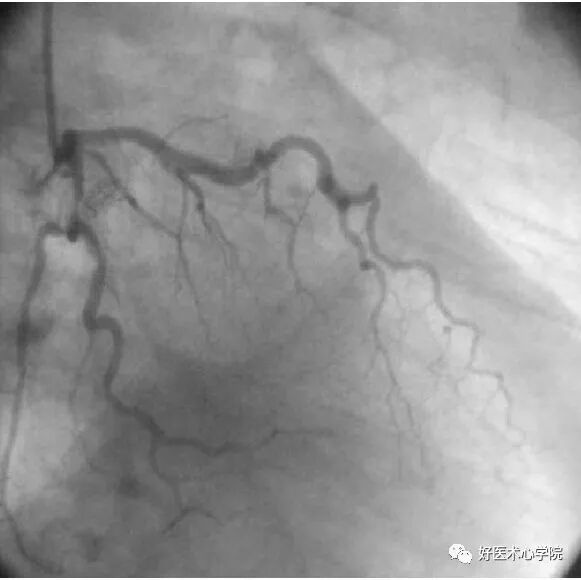

9. 侧支循环(Collateral Circulation)

当冠状动脉严重狭窄或阻塞时,近端灌注压明显下降,刺激侧支循环形成,血管远端被侧支循环逆向供血而显影。

造影导丝是什么珍藏 冠脉造影从流程到诊断,基础必备!_https://www.jmylbn.com_新闻资讯_第96张

侧枝:右冠脉→左前降支